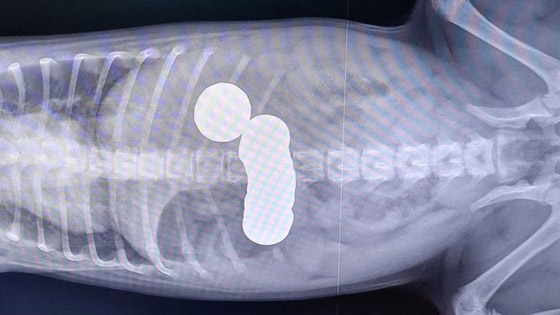

خضع جرو يبلغ من العمر 12 أسبوعًا لعملية جراحية طارئة بعد ابتلاع 20 قطعة نقدية من محفظة مالكتها. وقالت جمعية الأطباء البيطريين الخيرية في بيان اليوم، إن إيفانا مالكة ديزي، من ديربي بإنجلترا ، أصبحت قلقة عندما بدأ بالتقيؤ وتوقف عن الأكل. تم اصطحاب ديزي إلى الأطباء البيطريين حيث أظهرت صور الأشعة السينية أنها ابتلعت العملات المعدنية.

وقالت المؤسسة الخيرية إن العملية كانت ناجحة وتمكنت ديزي من العودة إلى المنزل في اليوم التالي بالأدوية. وفحص الأطباء البيطريون ديزي ورأوا أن معدتها تسبب لها الألم، وأضافت جمعية الأطباء البيطريين الخيرية أنه شوهد بنسين من العملة البريطانية في قيئها، مما أثار الشكوك حول وجود انسداد، لذلك تم تخديرها وتصويرها بالأشعة السينية. وأظهرت صور الأشعة السينية أنها ابتلعت 20 قطعة نقدية من فئات مختلفة، وقالت إيفانا: "لم أصدق ذلك عندما اتصلت جمعية الأطباء البيطريين الخيرية لتخبرني أن ديزي ابتلعت الكثير من العملات المعدنية.